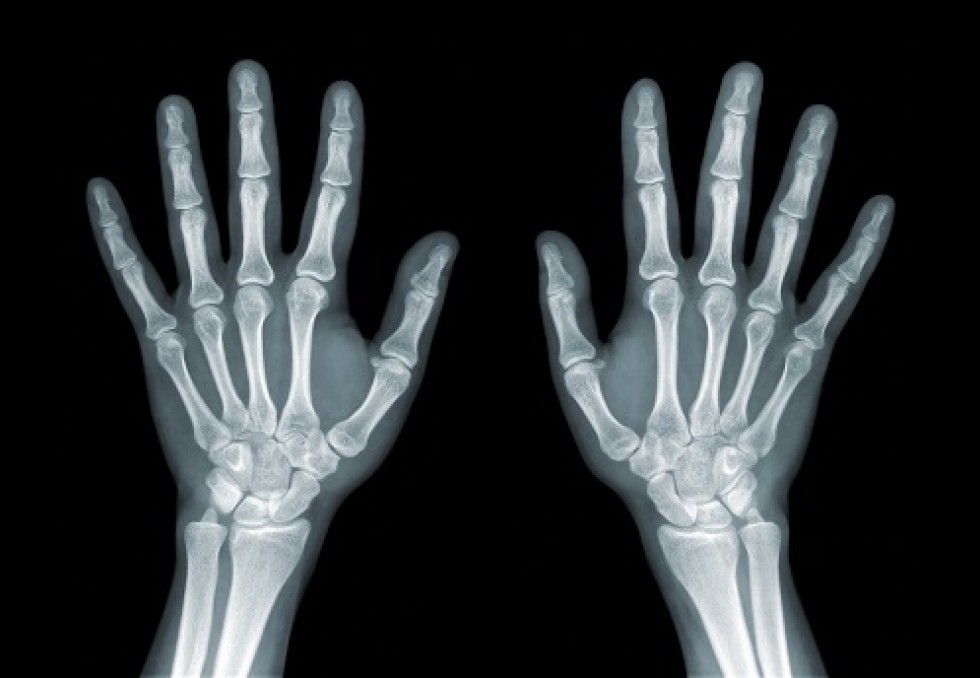

Mardi 12 mars, le Conseil constitutionnel se penchait sur le sort des tests osseux employés pour déterminer l'âge des mineurs étrangers isolés, dans le cadre d'une question prioritaire de constitutionnalité soulevée par des associations de défense des migrants. Il devra statuer sur la légalité de la procédure, dans une affaire impliquant un jeune Guinéen, Adama S., arrivé en France en 2016. La procédure, décriée pour son manque de fiabilité, joue un rôle déterminant dans le devenir des jeunes migrants arrivés seuls sur le territoire. Jugés mineurs, il relève de l'aide sociale à l'enfance et ne peuvent être expulsés du territoire. Dans le cas contraire, ils feront l'objet de la procédure classique, qui se solde souvent par un rejet de la demande d'asile. Un véritable couperet pour les personnes concernées.   Une loterie médicale Depuis l'interdiction de l'examen du développement pubertaire en mars 2016, l'évaluation de l'âge repose principalement sur l'estimation de l'âge par la méthode dite de Greulich et Pyle, conçue pour détecter des troubles de la croissance ou de la maturation osseuse. L'examinateur, radiologue ou pédiatre spécialisé, s'appuie une radio de la main gauche et du poignet de la personne, qu'il compare à des données de référence compilées sur des adolescents américains entre 1931 et 1942. La procédure est notoirement peu fiable, surtout après l'âge de quinze ans. De ce fait, l'Académie de médecine, la Société français de pédiatrie, ou encore la Société européenne de radiologie pédiatrique se sont prononcées contre son utilisation pour déterminer la majorité des jeunes migrants. Pour les associations, le recours à cet examen constitue une procédure arbitraire contraire aux droits de l'enfant. C'est sur la base de ces éléments que les "Sages" devront trancher sur la légalité de l'examen, auquel on ne connaît pas d'alternative fiable. Leur décision sera rendue publique le 21 mars. [Avec AFP]